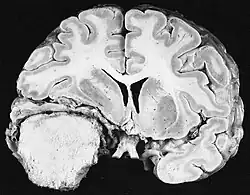

As ferramentas de diagnóstico por imagem radiológica destacam a mudança no tecido neoplásico em comparação com o parênquima cerebral normal (através de alterações na densidade do tecido fotografado eletronicamente na TC e na intensidade do sinal na RM). Como a maioria dos tecidos patológicos, os tumores também são reconhecidos por um acúmulo aumentado de água intracelular. Na tomografia computadorizada aparecem hipodensa, ou seja, de menor densidade que o parênquima cerebral, na tomografia de ressonância magnética nuclear com relaxamento spin-lattice T 1 hipointenso e em relaxamento spin-spin T 2 bem como a ponderação de prótons (PD) hiperintensa.

A tomografia computadorizada do cérebro normalmente mostra uma massa de tecido que pode ser realçada por qualquer contraste. Na TC, os gliomas de baixo grau geralmente parecem isodensos ao parênquima normal e, portanto, podem não apresentar realce pelo contraste. Da mesma forma, lesões na fossa posterior do crânio são difíceis de identificar na TC. Consequentemente, os resultados dessa tomografia isoladamente nem sempre são suficientes para fins diagnósticos. Em casos duvidosos, o uso da ressonância magnética mais sensível é essencial.

Na ressonância magnética, um tumor intracraniano aparece como uma lesão maciça que pode se tornar mais luminescente após o uso do agente de contraste. No entanto, há sempre uma anomalia de sinal na ressonância magnética, que indica a presença de neoplasia ou edema vasogênico. Normalmente, o aumento da luminescência (realce pelo contraste) é indicativo de um tumor de grau mais alto de malignidade. Um anel contrastante é característico do glioblastoma, com a porção luminescente correspondendo à parte vital do tumor maligno e a área mais escura-hipointense à necrose tecidual.